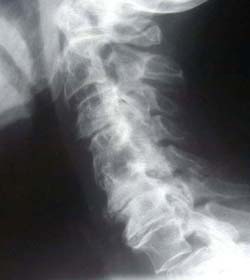

Phase Three Subluxation Degeneration

Phase Three degeneration develops when subluxations persist for 40 to 65 years. All findings from the previous stages now become more severe:

• Significant loss of normal spinal curvature

• Severely altered or collapsed disc spaces

• Extensive calcium deposits or bony overgrowths ("spurs" or "lipping")

• Marked reduction in movement

• Changes in the shape and integrity of the vertebrae

Most individuals in Phase Three experience symptoms, stiffness, or functional limitations.

Chiropractic reconstructive care in Phase Three often ranges from 2.5 to 3.5 years.

Although calcium deposits may remain, improvements in function and mobility are still common — the goal becomes restoring as much quality of movement and life as possible.